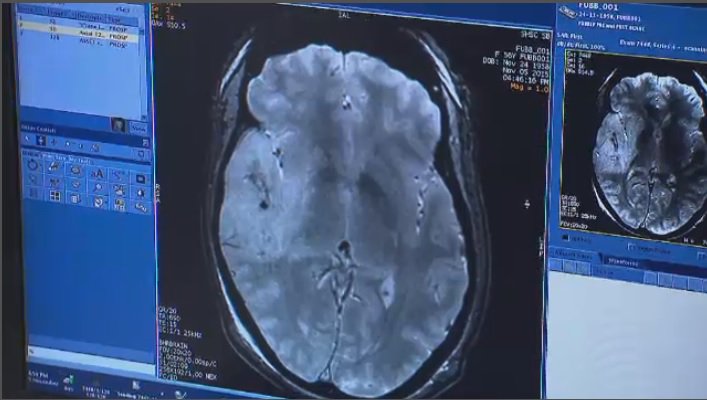

Published: Predictors of Lesion Cavitation After Recent Small Subcortical Stroke http://ow.ly/NUdp50xf6bI

#stroke#bloodbrain#mripic.twitter.com/aMEudIxYAj